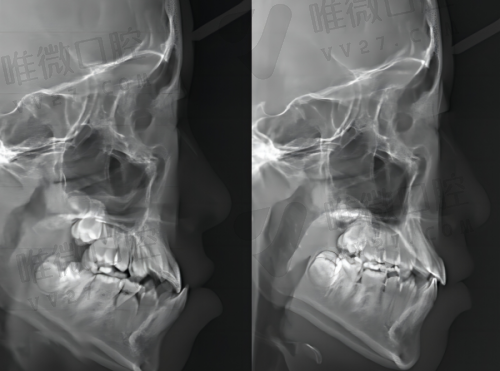

数字化种植技术

:通过CBCT精细测量骨量,3D打印种植导板